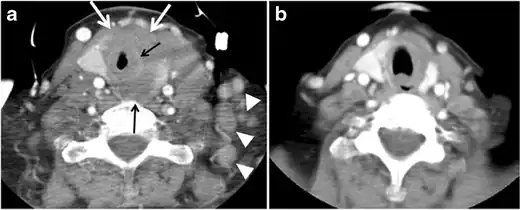

Fig. 7. A 51-year-old female patient post total thyroidectomy for PTC with elevated thyroglobulin measurement. an Axial non-enhanced CT scan of the neck at the level of the thyroid bed demonstrates a well-defined, rounded, homogenously dense soft tissue situated between the trachea and left internal jugular vein (white arrow). b Transverse ultrasound image of the neck demonstrates a well-defined, homogeneous, hypoechoic soft tissue nodule measuring 6 mm (white arrow) with no detected micro-calcifications. Biopsy showed a predominantly residual normal thyroid tissue with micro-foci of PTC.[1]

Fig. 8. A 48-year-old male patient post total thyroidectomy with PTC recurrence. a Transverse greyscale ultrasound of the neck demonstrates a left thyroid bed heterogeneous, predominantly hypoechoic irregular lesion with calcifications (white arrow). b A spot image of iodine 123 total body scan of the neck demonstrate a focus of abnormal radiotracer uptake at the left thyroid bed (Black arrows) between the annotated markers. c Enhanced axial CT scan of the neck demonstrates an enhancing large left thyroid bed mass (white arrow) with no calcifications. The lesion exerts a mass effect on the oesophagus (black arrow) and is inseparable from the trachea.[1]

Fig. 9. A 58-year-old male patient with persistence PTC at thyroid bed with hypervascular nodal metastasis. a–c Transverse greyscale and colour Doppler neck ultrasound demonstrate hypoehoic soft tissue in the left thyroid bed (white arrow in a). There are a heterogeneous enlarged lymph nodes at level 2 and 3 with markedly increased vascularity (white arrow in b and c). d–f Enhanced axial CT images of the neck demonstrate a 2.7 × 1.4 cm hypodense soft tissue lesion anterior to the left carotid sheath (white arrow). There are left-sided enhancing abnormal and enlarged lymph nodes at cervical level 2 and 3 (black arrows).[1]